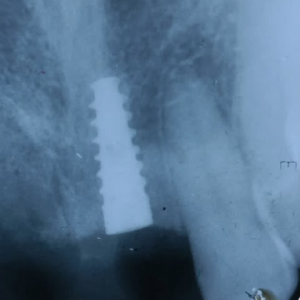

- Ridge Split surgeries for dental implants

- Guided Bone Regenerative procedures using membrane and bone grafts

- Conventional Implant Surgeries